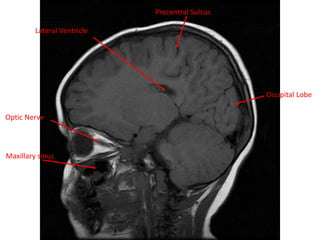

Precentral Sulcus

Lateral Ventricle

Occipital Lobe

Maxillary sinus

Optic Nerve Precentral Sulcus LateralVentricle Occipital Lobe Maxillary sinus